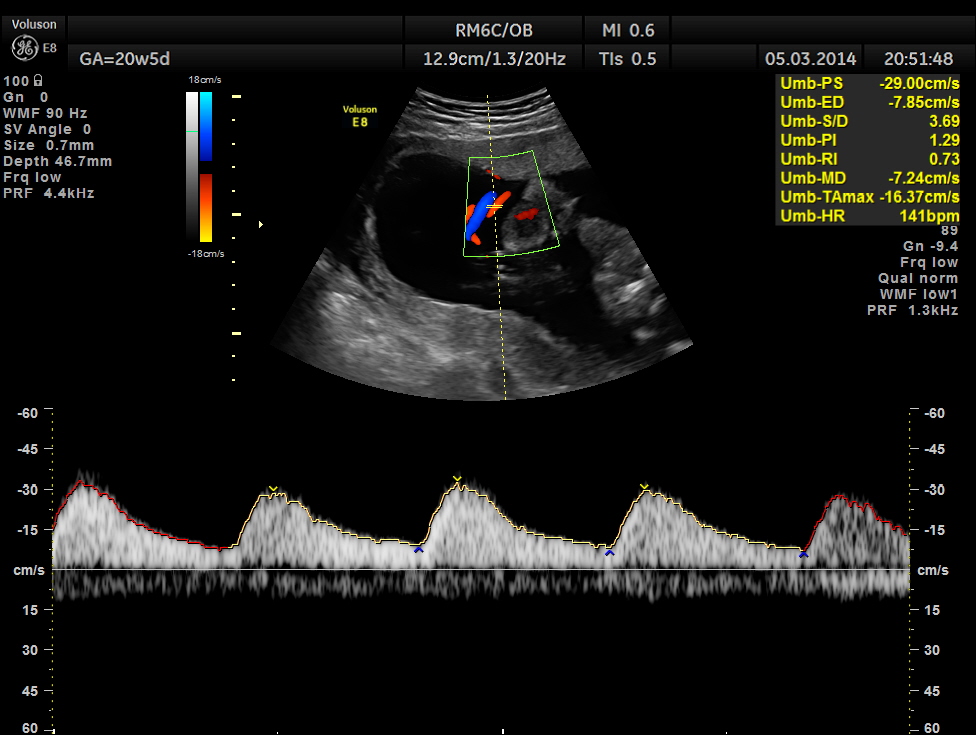

Umbilical artery doppler appears to be normal for the GA.

Spectral Doppler pictures are given below.

Umbilical arterial arterial P.I. and R.I. are high for the GA. and the cerebro placental ratio appears to be borderline > 1.0 and < 1.1 for the R.I.